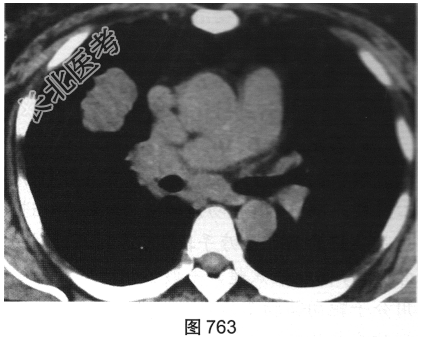

- 简答题2、患者行胸部CT检查,如图762、图763所示。胸部CT如图所示,超声心动图显示心功能降低,冠状动脉CTA除显示原支架内轻度狭窄外,未见其他异常。为明确病变性质,请问下一步应进行哪些检查?